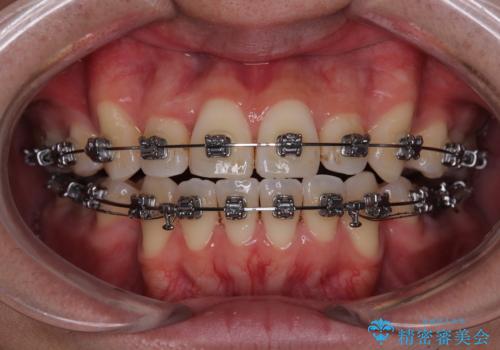

- 矯正装置

- メタルブラケット

- 2年